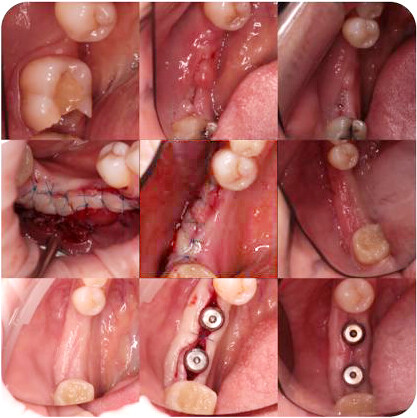

В рамках курса Вы получите полный обзор современных методик восстановления эстетики мягких тканей вокруг имплантатов. Курс включает в себя анализ всех существующих на данный момент техник и методов их проведения, а так же особенности их применения в различных случаях. Вы также ознакомитесь с малоинвазивными методами. В итоге Вы станете более уверенных и компетентным специалистом в области пластики мягких тканей и сможете обеспечить своим пациентам наивысший уровень качественной стоматологической помощи.

- Биологическая ширина на имплантате

- Мягкие ткани , окружающие имплантатов

- Мягкие ткани , окружающие зубов

- Биотипы мягких тканей вокруг имплантатов

- Донорские зоны

- Ведение донорской зоны

Клинические кейсы: